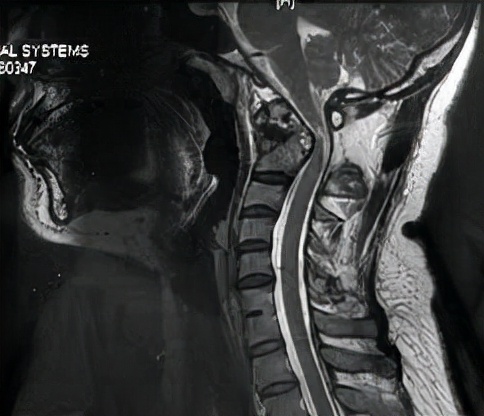

检查显示严重的寰枢椎固定脱位,脊髓也受到压迫。

牵引复位,螺钉固定,植骨融合,效果还是非常好。我们的手术安全并且出血极少。